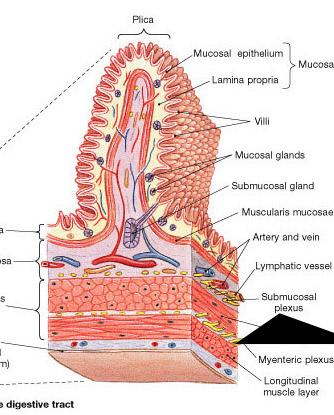

Goblet cells

Inner circular layer (of muscular externa)

Lacteal

Lumen

Microvillus (s.) Microvilli (pl.)

Mucosa

Outer longitudinal layer (of muscular externa)

Serosa

Submuscosa

Villus (s.) Villi (pl.)